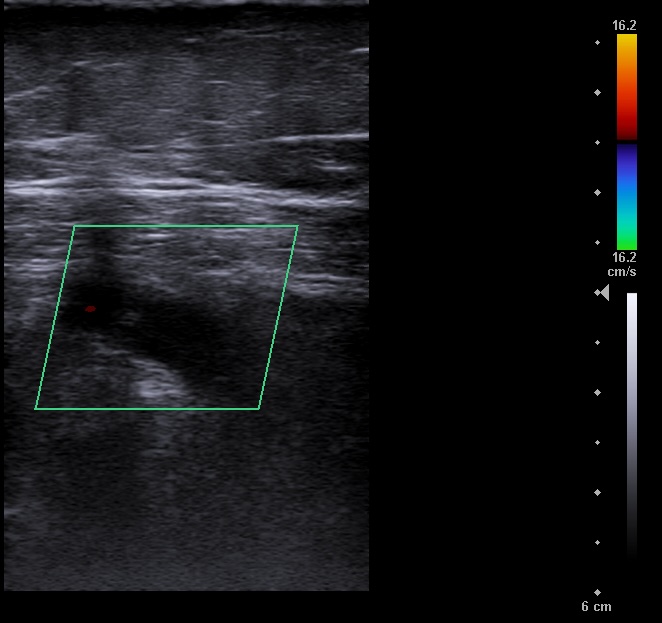

En la ecografía se aprecia vena femoral común, vena femoral superficial, vena safena mayor y vena safena menor con diámetro y flujo normal, llenado total de la luz venosa con el Doppler color y compresibilidad adecuada.

Vena poplitea no compresible, con material ecogénico en su interior y ausencia de flujo con Doppler color.